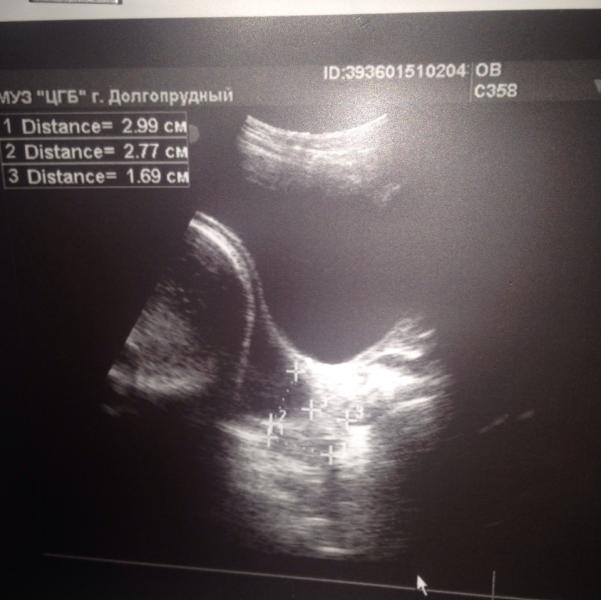

Девочки, у меня паника, зуб на зуб не попадает, меня всю трясёт и мурашки по коже..... Сделала Узи, срок 34,2. Диагноз ицн давно, стоит пессарий. НО!!!! Пузырь уже в цервикальном Канале, закрытая часть шейки 15 мм!!!! (Длина шейки 29 мм, внутренний зев 2,8 см). Все держится на честном слове! Там не просто пролобирование пузыря, там как ведро, наполненное водой, уже в шейке!!!! Я в шоке! При этом ребёнок 2500, вод хорошее количество, плацента молодая. Все вот хорошо, кроме моей гребанной шейки!!!! Рано вещь ещё, рано!!!! Узистка сказала, чтобы я от дома далеко не отходила и вообще есть вероятность, что я не доеду до Московского роддома (до 17-го ехать 15 минут).... Ппц! Меня трясёт всю! А направление только в Долгопрудненский роддом, который настолько ужасный и бестолковый, что можно его сравнить с полем ("ехать в поле рожать")... На фото - то самое "ведро"